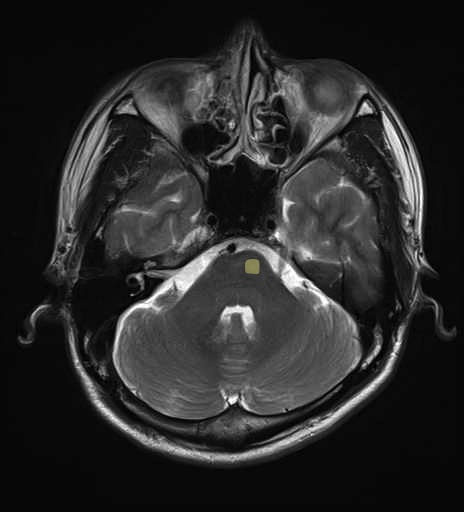

運動系 錐体路系に色を付けました。

■皮質脊髄路(いわゆる錐体路):一次運動野から脊髄遠隔の下位運動ニューロン細胞体まで

■皮質核路:一次運動野から橋及び脊髄神経核まで